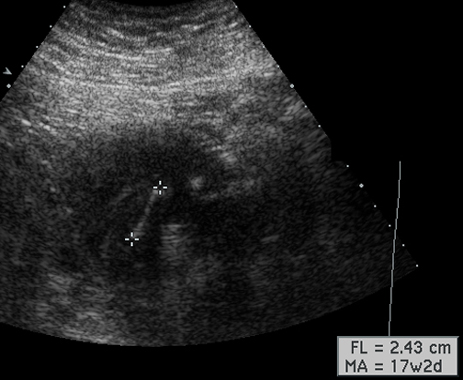

Identify fetal femur. How do you use the length of fetal femur. Answer

Placenta, Tibia, Femur